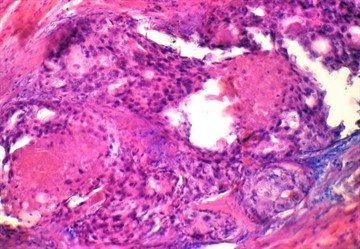

Нередко при цитологическом исследовании выявляется доброкачественный состав клеток опухоли. Если в анализируемом материале обнаруживаются макрофаги, нейтрофилы, гистиоциты (вид макрофагов, которые у здоровых людей присутствуют в соединительной ткани), то это говорит о протекании воспалительного процесса. Распространенным диагнозом у женщин является фиброзно-кистозная болезнь молочных желез.

Поражение характеризуется изменениями строения паренхимы, стромы, образованием кистозных элементов. Стимулом для развития патологического процесса выступает дисбаланс гормонов.

В результатах гистологического обследования при наличии фиброзно-кистозного мастита присутствуют такие изменения:

• единичные пенистые макрофаги;

• ксантомные клетки;

• признаки внутрипротоковой пролиферации эпителия разной выраженности;

• голоядерные клетки.